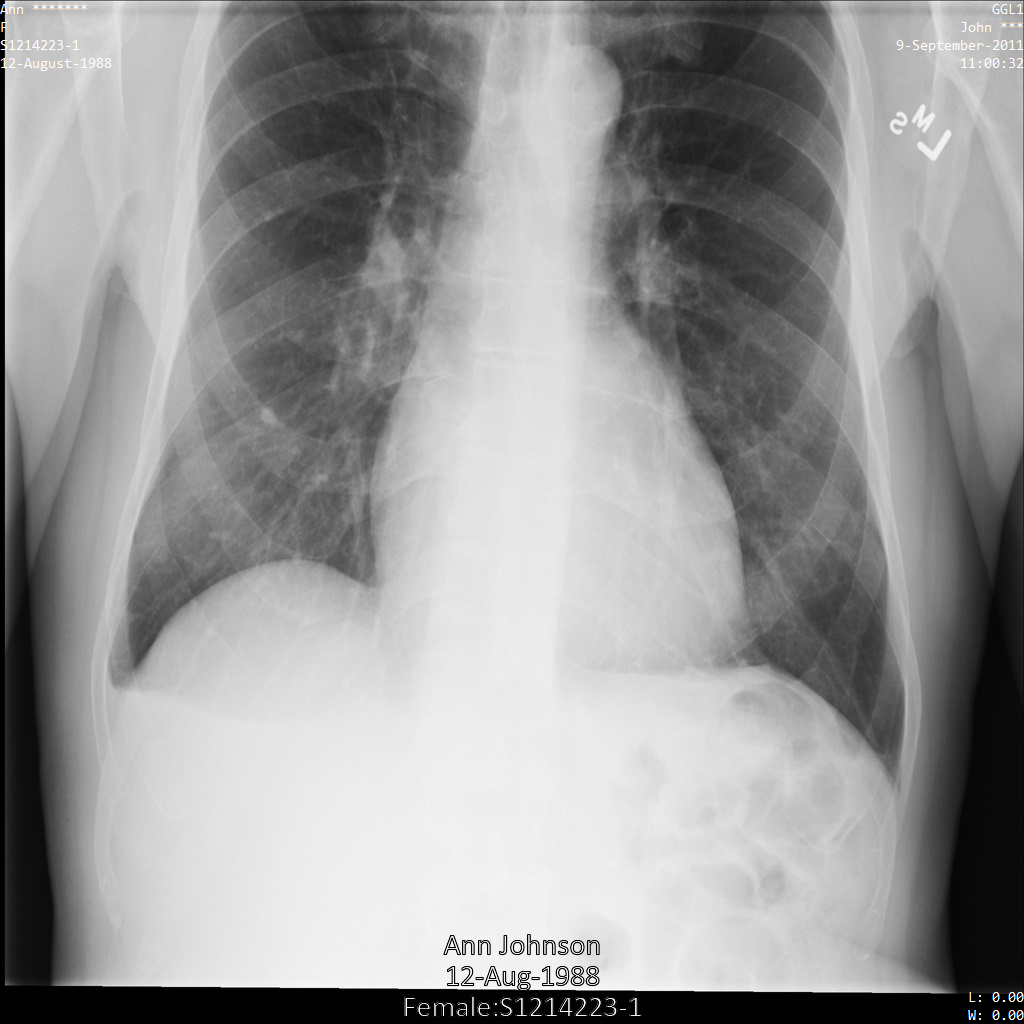

以下の各セクションでは、DICOM データを匿名化するさまざまな方法について、例を示しています。また、それぞれの例で匿名化された出力画像を示しています。各例では、入力として以下の元画像を使用しています。

各匿名化オペレーションからの出力イメージをこの元のイメージと比較して、オペレーションの効果を確認できます。

Cloud Healthcare API に画像を送信すると、画像は次のように表示されます。画像の上部隅に表示されているメタデータは削除されていますが、画像の下部にある焼き付き保護対象保健情報(PHI)は残ります。焼き付きテキストも削除するには、画像の焼き付きテキストを削除するをご覧ください。

Cloud Healthcare API に画像を送信すると、画像は次のように表示されます。removelist に含まれるタグのうち、PatientBirthDate のみが画像から削除されます。これは、画像に表示されるメタデータに対応する removelist からの唯一のタグのためです。

画像の上部隅にある PatientBirthDate は、removelist の構成に従って削除されていますが、画像の下部の焼き付き PHI は残ります。焼き付きテキストも削除するには、画像の焼き付きテキストを削除するをご覧ください。

ATTRIBUTE_CONFIDENTIALITY_BASIC_PROFILE タグフィルタ プロファイルを使用して画像を Cloud Healthcare API に送信すると、画像は次のように表示されます。画像の上隅に表示されているメタデータは削除されていますが、画像の下部の焼き付き PHI は残ります。焼き付きテキストも削除するには、画像の焼き付きテキストを削除するをご覧ください。

REDACT_ALL_TEXT オプションを使用して Cloud Healthcare API に画像を送信すると、画像は次のように表示されます。画像の下部にある焼き付きテキストは削除されましたが、画像の上端にあるメタデータは残ります。メタデータも削除するには、DICOM タグの匿名化をご覧ください。

次の画像は、患者の X 線を秘匿化していない状態を示しています。

REDACT_SENSITIVE_TEXT オプションを使用して Cloud Healthcare API に画像を送信すると、画像は次のように表示されます。